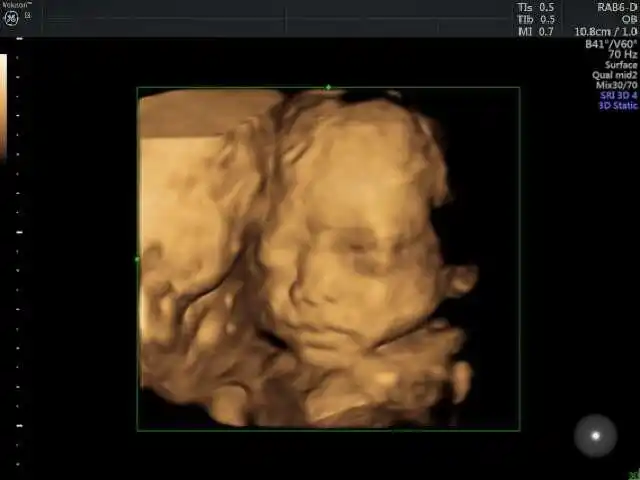

今天去做四维彩超,问医生给宝宝买什么衣服合适,医生说跟我差不多是